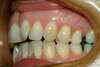

Cas de Damon avec attaches transparentes

Intra Orale Face